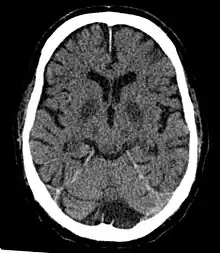

- Silent stroke is a stroke which does not have any outward symptoms, and the patient is typically unaware they have suffered a stroke. Despite its lack of identifiable symptoms, a silent stroke still causes brain damage and places the patient at increased risk for a major stroke in the future. In a broad study in 1998, more than 11 million people were estimated to have experienced a stroke in the United States. Approximately 770,000 of these strokes were symptomatic and 11 million were first-ever silent MRI infarcts or hemorrhages. Silent strokes typically cause lesions which are detected via the use of neuroimaging such as fMRI.[13][14] The risk of silent stroke increases with age but may also affect younger adults. Women appear to be at increased risk for silent stroke, with hypertension and current cigarette smoking being predisposing factors.[15][16]

- Global cerebral ischemia – A complete stoppage of blood flow to the brain.

- Cerebral infarction – A "stroke", caused by complete oxygen deprivation due to an interference in cerebral blood flow which affects multiple areas of the brain.